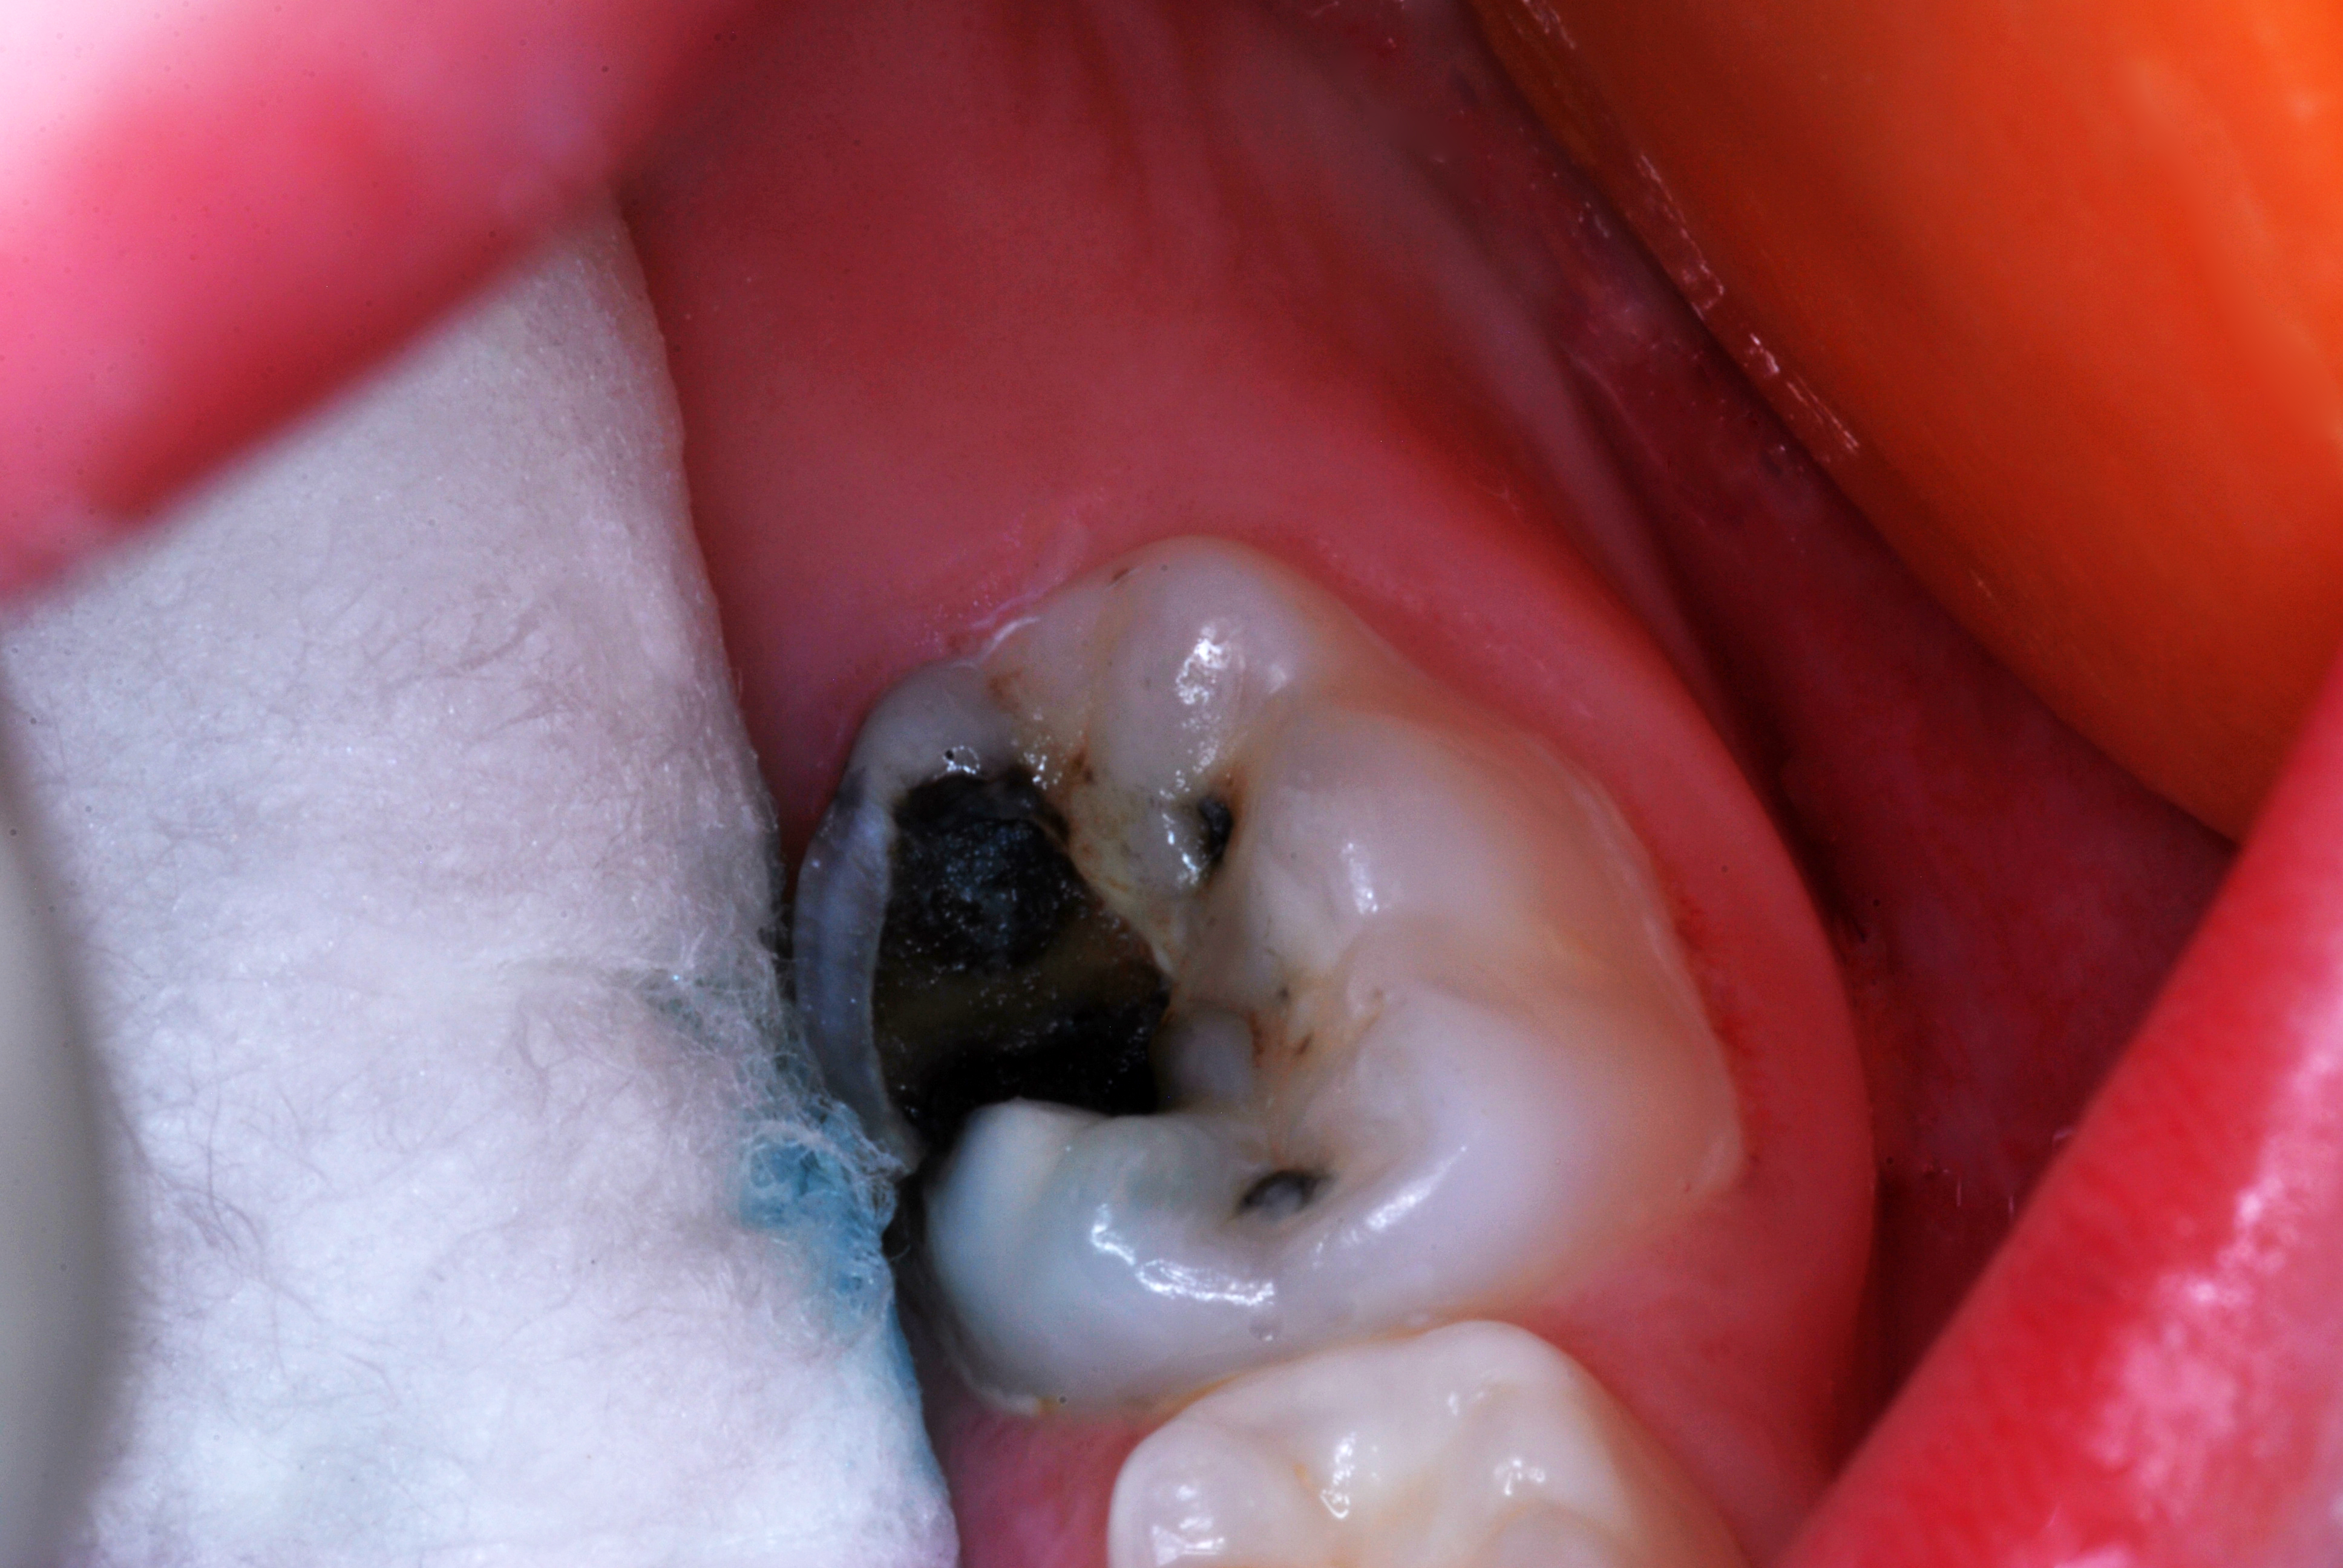

(1.) Hypocalcified/carious first molar, 12 months after SDF application.

Figure 1